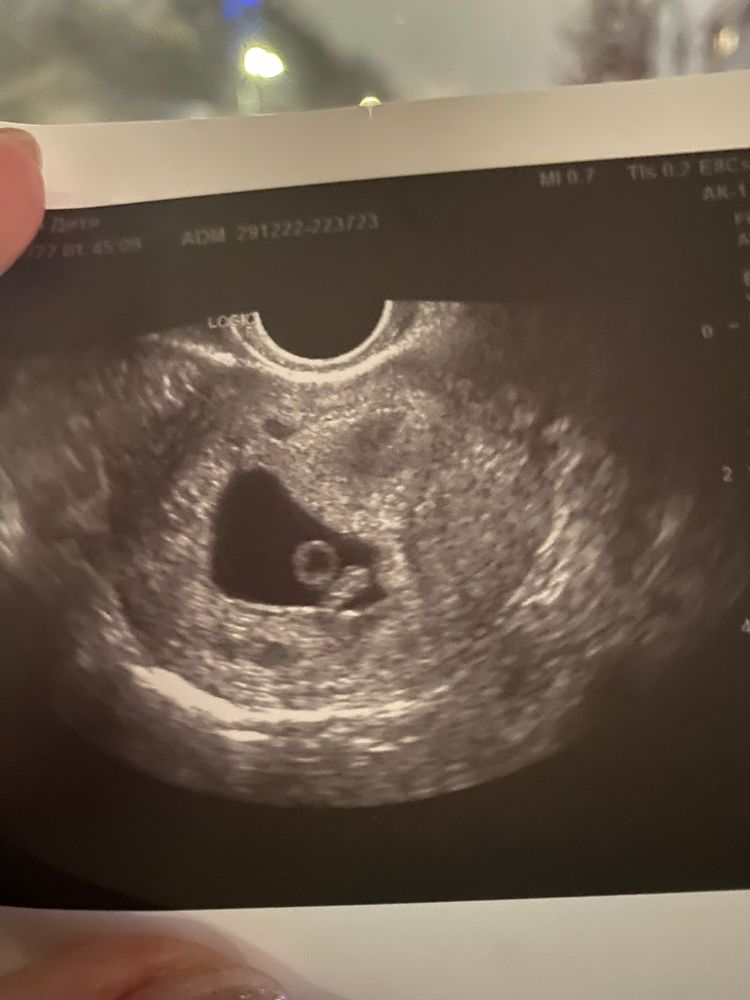

36 дпп не видно сердцебиения

Так вот именно что они считают что срок у меня 5 недель и тогда типо все норм что не слышно сердца. Я сними спорю говорю уже же 7 недель почти 8. Нет все равно 5 и размеры плотного яйца точнее двух не 7 недельные. Как такое может быть не понимаю

К сожалению ничего хорошего и не понятно почему они тянут и сохранчют. На 26-28 дпп должен быть эмбрион 8-10 мм и чсс не менее 120 ударов У вас 36 дпп и это не 5 недель а 7.

У вас уже не 5 недель,а 5+1 от подсадки+возраст эмбриона 5 дней+ 2 недели и =7+6 акушерских,на таком сроке уже эмбрионы по 15 мм с ручками и ножками,у вас уже должны быть давно эмбрионы и сб,даже на хромом аппарате

На 29 дпп, уже был виден эмбриончик с сердечком. Переделать УЗИ, возможно аппарат старый и не увидели, но на вашем сроке уже должны быть эмбрионы

Странно как-то считают у Вас  У меня перенос был 24.04.2023, один эмбрион пятидневка, на 29 дпп (23.05.2023) видно было и эмбрион, и сердцебиение, и срок тогда написали 6+1 по переносу или 6+6 по месячным